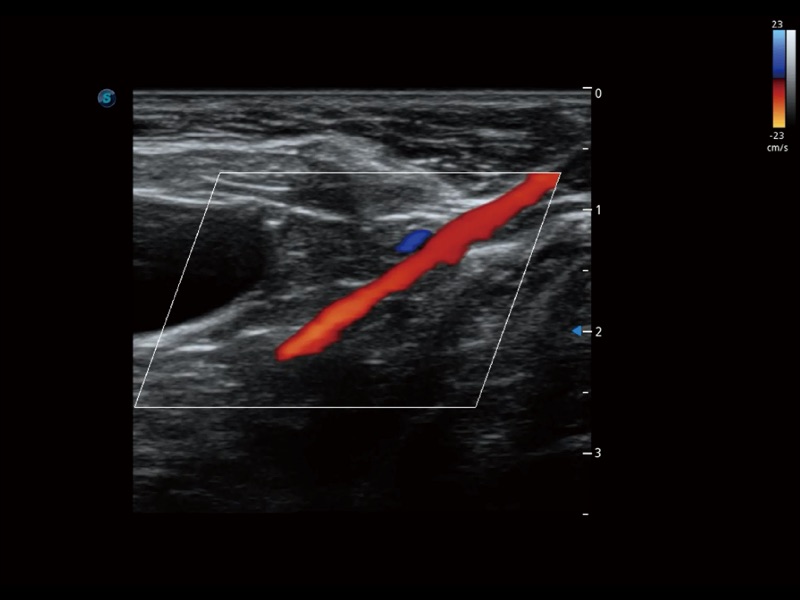

通过色彩血流和实时宽景相结合,可观察到完整的静脉或动脉的血流,方便医生检查。实时扫查过程中,如有任何操作失误也可以很容易地进行回扫擦除,而不会中断扫查。

为精细结构及组织边缘提供高清晰度的图像和更大的成像视野。帮助减轻医生的用眼疲劳,快速精准获得测量的数据。

ProPet 70 全新的动物超声智能软件和丰富的探头群,为动物医生提供了高清晰度和精细分辨率的图像,无论在宠物、马科、畜牧还是实验室动物等应用中都可以轻松应对,为您的日常工作带来满意的体验。